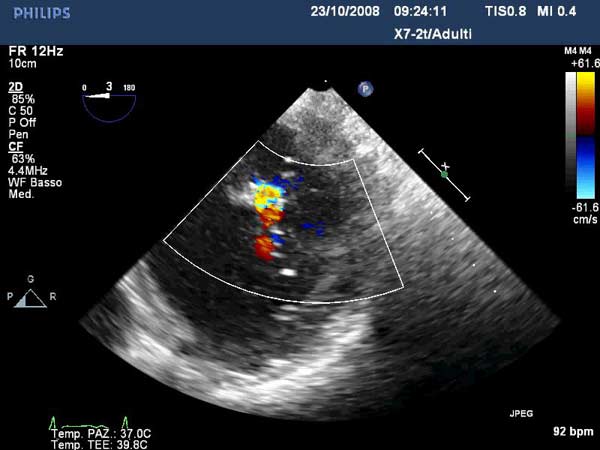

Figure 5

Figure 6

In absence of controlled clinical trial data which are forthcoming from the EVEREST II randomized study, the indications for the MitraClip therapy are currently based on registry experience and will evolve as the technique improves, experience is growing and the data to demonstrate efficacy and safety becomes available. At this time, the best indication for the MitraClip therapy is for symptomatic patients with clinically significant functional or degenerative MR who are at high or increased risk for open heart surgery. From a pure technical standpoint, the procedure so far has only been demonstrated in a subgroup of patients with specific anatomical characteristics which are summarized below and shown in Figure 3. Anatomic suitability is assessed by transesophageal echocardiography, and mitral regurgitation should originate from the central portion of the valve involving the A2-P2 segments, since the device is not ideal to work in the commissures at this time; the mechanism of MR can be either a prolapse/flail or MR due to restricted leaflet motion unrelated to rheumatic disease; the separation between the two leaflets at the site of regurgitation should be limited; severe annular dilatation and/or severe calcification should be absent or is relevant. In case of flail, the flail segment width should be less than 15 mm, and the flail gap less than 10 mm. Figure 4 is a 3D echo image of a patient with posterior leaflet prolapse selected for MitraClip therapy. In case of functional MR, the leaflets should have a minimal residual tissue available for coaptation with the MitraClip device. Figure 5 shows 2D color Doppler jet extension over the coaptation line at TEE short axis transgastric view, while Figure 6 shows the tenting area and the coaptation depth of a patient undergoing MitraClip implant.